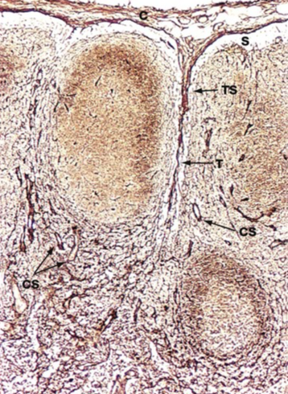

26

what are the borders and arrows indicating

nasopharynx are the borders far left arrow is adenoid tonsils middle arrow is tubal tonsils right arrow is the opening of the eustachian tube